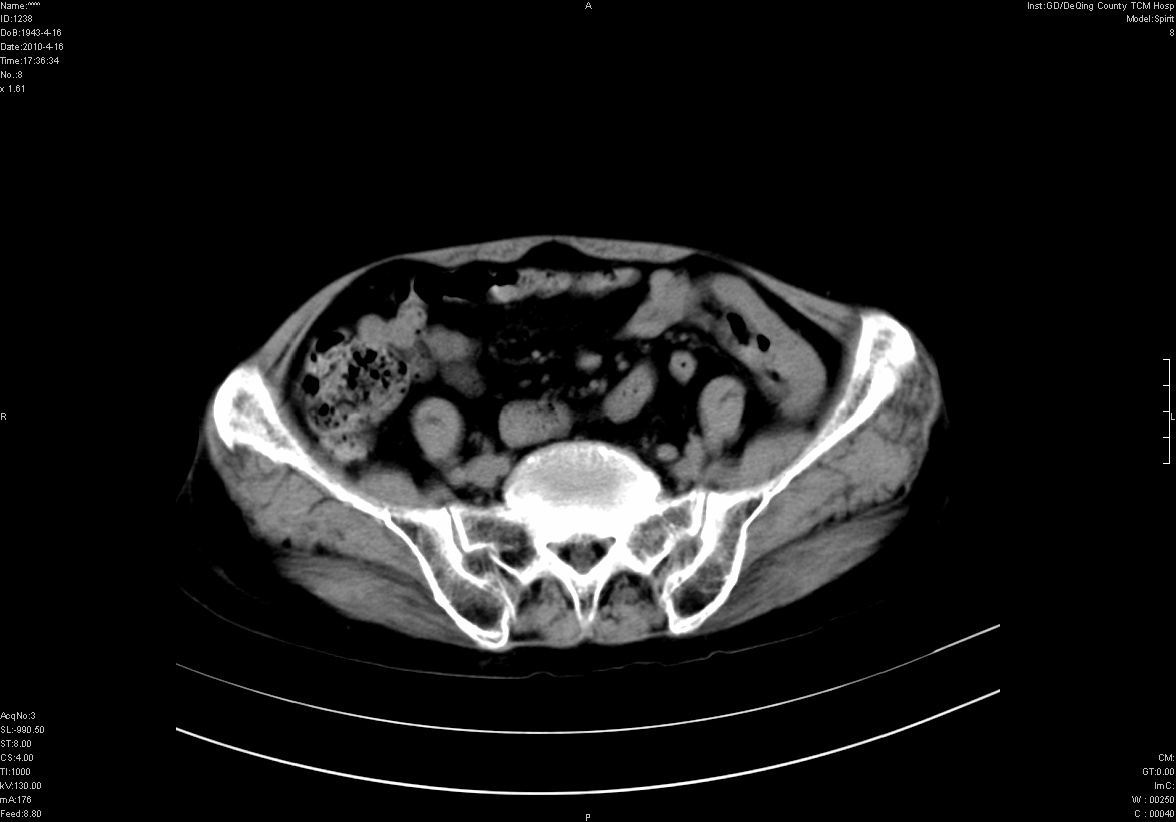

标题: CT25796:女,60岁,腹痛5天,请会诊??? [打印本页]

标题: CT25796:女,60岁,腹痛5天,请会诊???

是要我考虑粪石吗?引起阑尾炎

以下是引用xzh825在2010-4-16 18:19:00的发言:[br]是要我考虑粪石吗?引起阑尾炎

有可能。

钙化灶

不太像畸胎瘤,粪石。